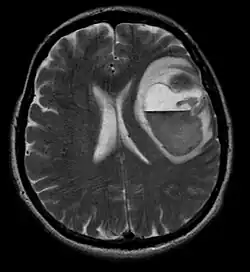

A tomografia computadorizada (TC) e a ressonância magnética (RM) podem detectar efetivamente uma neoplasia no cérebro. A RM é mais sensível que a TC para identificar lesões, mas contraindicações para pacientes com marcapasso cardíaco, próteses incompatíveis, clipes metálicos e outros. A TC continua sendo o método de escolha para detectar calcificações dentro de lesões ou erosões ósseas da calota craniana ou da base. A utilização de agentes de contraste, que são iodados no caso da TC e paramagnéticos ( gadolínio ) no caso da RM, permite a aquisição de informações sobre a vascularização e integridade da barreira hematoencefálica, uma melhor definição do tumor tumoral comparado ao edema circundante e à geração de hipóteses sobre o grau de malignidade . O exame radiológico também permite avaliar os efeitos mecânicos e consequentes alterações nas estruturas cerebrais decorrentes do tumor, como hidrocefalia e hérnias, cujos efeitos podem ser fatais. Finalmente, na preparação para a cirurgia, esse diagnóstico pode ser usado para determinar a localização da lesão ou a infiltração do tumor em áreas vitais do cérebro. Para isso, a RM é mais eficiente que a TC, pois pode fornecer imagens tridimensionais.

No tecido tumoral, em geral, a maior proporção de realce pelo contraste se deve à barreira hemato-tumor particular que permite a passagem de iodo (TC) e gadolínio (RM) para o espaço intersticial extravascular intratumoral. Isso aumenta o sinal (densidade ou intensidade) do tumor. No entanto, deve-se ter cuidado para garantir que o realce do contraste não diferencie definitivamente a neoplasia do edema periferida. De fato, o achado anátomo-patológico no tecido tumoral de glioma infiltrante maligno, como no glioblastoma e no astrocitoma anaplásico, também mostra além do edema vasogênico causado pela destruição da barreira hematoencefálica pelo tumor. Esta última condição clínica é pouco detectável pelo diagnóstico por imagem.

Na ressonância magnética, um tumor intracraniano aparece como uma lesão maciça que pode se tornar mais luminescente após o uso do agente de contraste. No entanto, há sempre uma anomalia de sinal na ressonância magnética, que indica a presença de neoplasia ou edema vasogênico. Normalmente, o aumento da luminescência (realce pelo contraste) é indicativo de um tumor de grau mais alto de malignidade. Um anel contrastante é característico do glioblastoma, com a porção luminescente correspondendo à parte vital do tumor maligno e a área mais escura-hipointense à necrose tecidual.